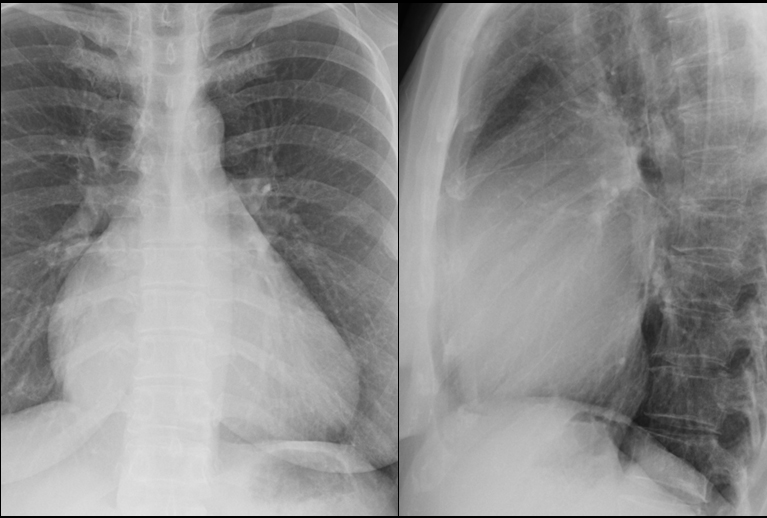

Tricuspid insufficiency